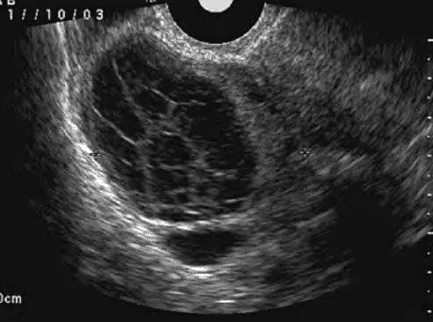

Phần tiêu đề “Nang hoàng thể”Hình ảnh “Hoàng thể xuất huyết trên siêu âm”.

Hoàng thể xuất huyết:

- Khi hình thành hoàng thể, mạch máu xâm nhập lòng nang, xuất huyết thường tự cầm. Nếu xuất huyết không giới hạn, hoàng thể to > 3 cm.

- Nếu vỡ nang, có thể chảy máu ổ bụng, cần phẫu thuật cầm máu. Nếu chỉ căng nang, gây đau, xử trí giảm đau và theo dõi.

- Bệnh nhân không dùng COC, có kinh đều, đau cấp hạ vị ở pha hoàng thể. Một số hiếm chảy máu nhiều cần mổ.

- Nhóm nguy cơ: Người dùng thuốc chống đông hoặc rối loạn đông máu.